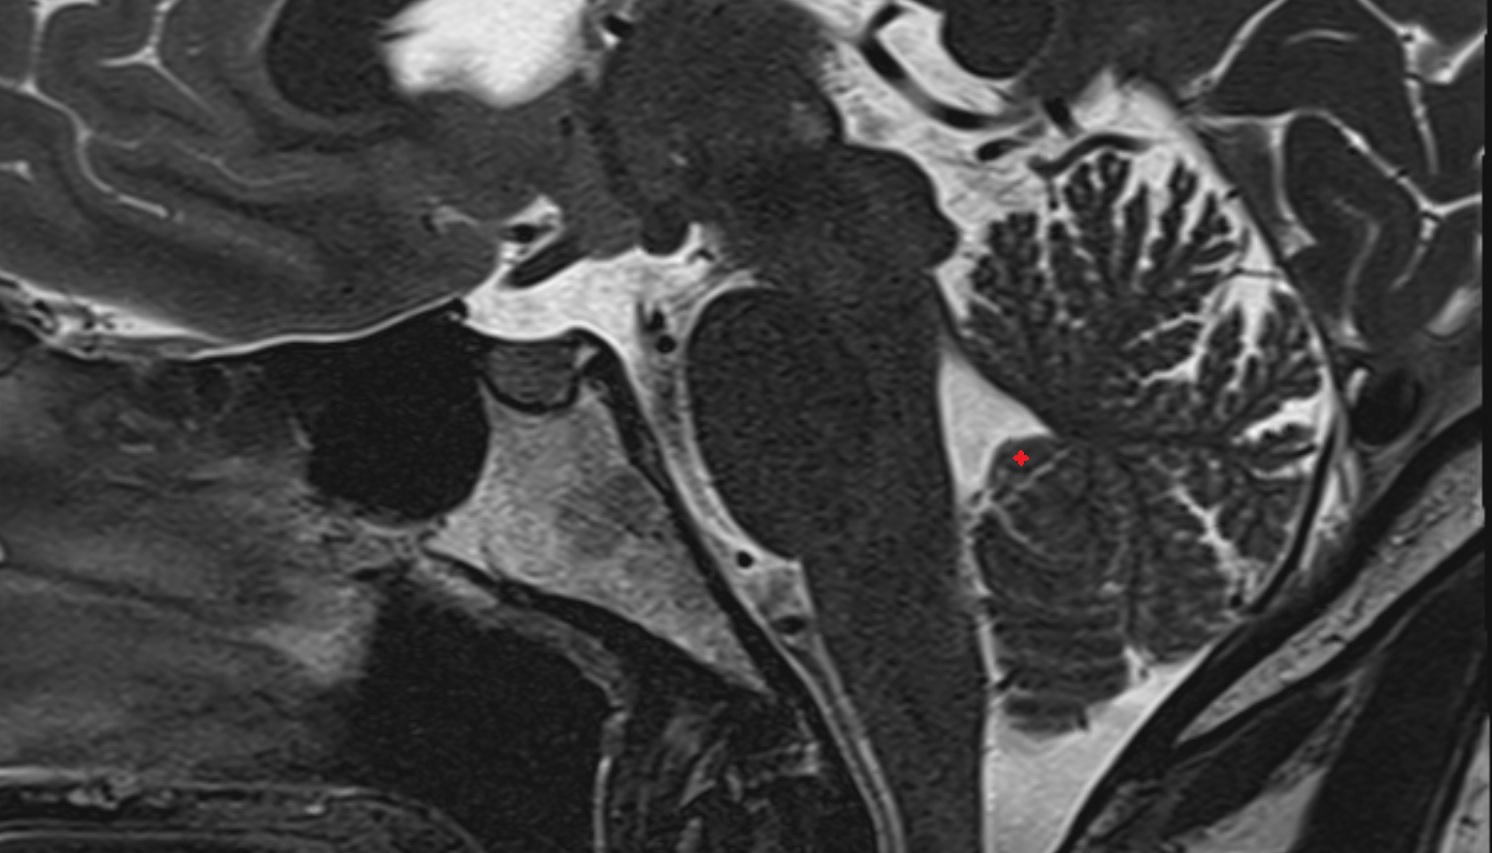

- Arbor Vitae (Cerebellar White Matter)

- Cerebellum

- Central lobule (II & III) of Cerebellum

- Culmen (IV, V) of Cerebellum

- Declive (VI) of Cerebellum

- Folium (VII) of Cerebellum

- Tuber of vermis (VII)

- Pyramid of vermis (VIII)

- Uvula of vermis (IX)

- Nodule of vermis (X)

- Cerebellar tonsil (H IX)